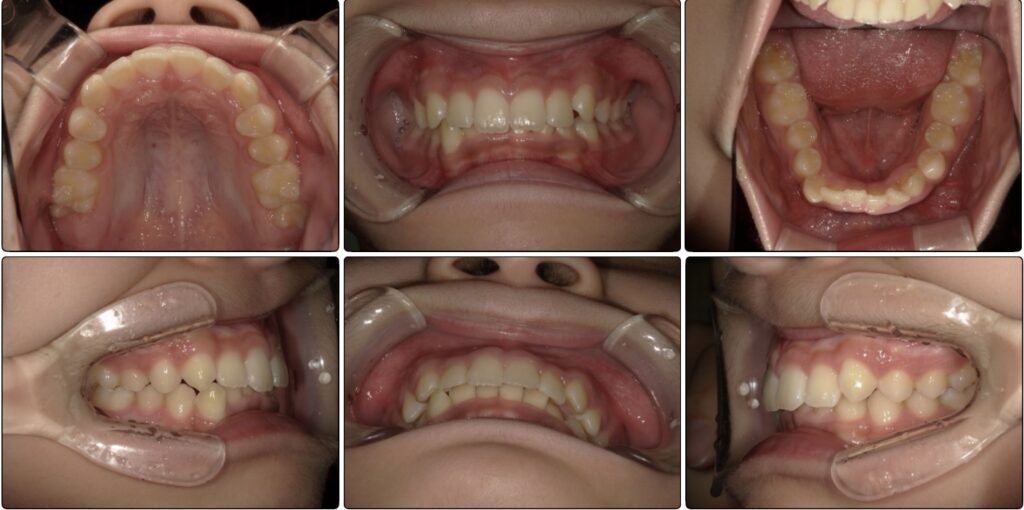

始めの検査の時の写真です。

下の歯があまり見えておらず、横からの写真を見ると上の歯に覆い被さっているように見えます。

過去にこの男の子は他院で上の歯並びのみ矯正をしていました。

確かに上の歯は綺麗ですが、下の歯にはガタつきが残っています。

この時既に歯の生え変わりは終わっており全て永久歯の状態です。